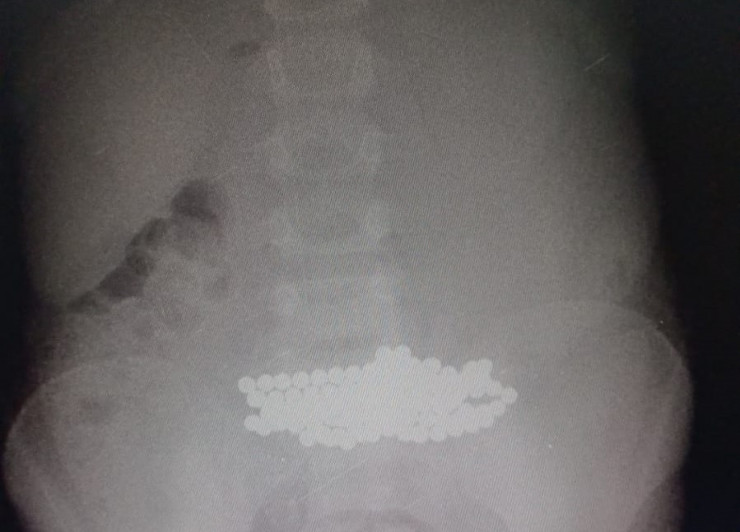

В столице медики извлекли из желудка семилетней девочки 100 магнитов. Сейчас жизни ребенка ничего не угрожает, передает Tengrinews.kz со ссылкой на сайт акимата Нур-Султана.

"На прошлой неделе провели операцию девочке, которая поступила в больницу для прохождения магнитно-резонансной томографии (МРТ). Во время осмотра в носу ребенка врачи обнаружили магниты, уже с перфорацией перегородки носа. После чего ребенок был направлен на рентген-исследование, которое выявило огромное скопление магнитов в желудке. В итоге мы вытащили более 100 мелких магнитов", - говорит Ринат Байгиреев.